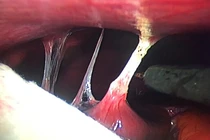

(khoahocdoisong.vn) - Hội chứng Fitz-Hugh-Curtis (FHC) là một biến chứng của bệnh lý viêm nhiễm vùng tiểu khung gây nên viêm quanh gan và có thể dẫn đến dính bao gan với phúc mạc. Bệnh dễ bị chẩn đoán nhầm và bỏ sót nên chị em trong độ tuổi sinh đẻ cần chú ý.